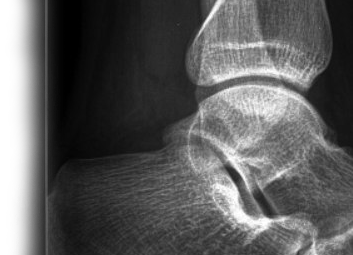

Рентгенография голеностопного сустава – важный метод прицельного исследования, который позволяет оценить состояние голеностопного сустава. Диагностическая услуга выполняется в двух проекциях.

Рентген позволяет исключить патологию голеностопного сустава костно-травматического, дегенеративно-дистрофического, опухолевого генеза.